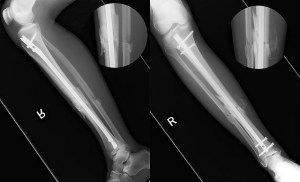

Finally I was cleared by the neurology department and I became an orthopedic patient. With my broken tibia and fibula, humorous, and pelvis, I needed surgery. As I went into surgery I asked the physician’s assistant, “Will I run again?” She told me that in one year I would be 99.7% better and, yes, I should be able to run again. A rod was put in my leg, my shoulder was set, and Pegleg was born.